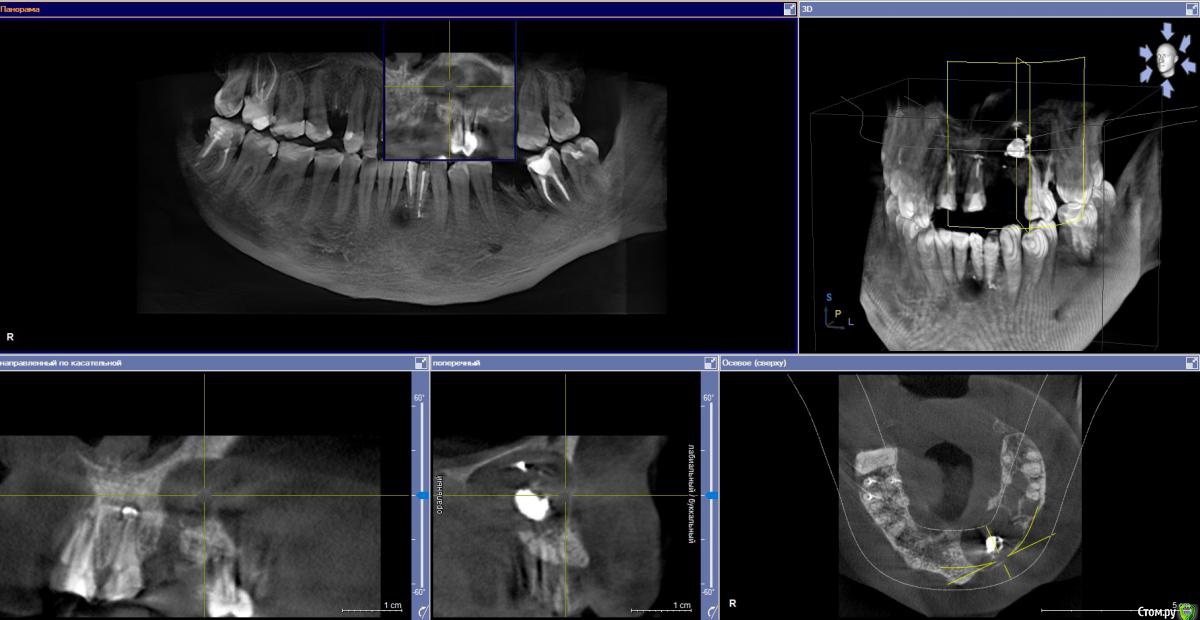

Ponchik Опубликовано 17 ноября, 2015 Поделиться Опубликовано 17 ноября, 2015 (изменено) Пациента ничего не беспокоит. В анамнезе травма 2 сегмента 7 лет назад. Пришел с целью протезирования. Ортопед удалили 22 и направил кисту убрать. Сделали прицельный.Потом захотелось КТ. КТ вышло не очень, но общее представление составить можно. Появились вопросы. На сколько велика вероятность встречи с синусом? Стоит делать амбулаторно? Опыт до этого - цистэктомии в пределах 1-2 зубов. Думаю куда направить. Изменено 17 ноября, 2015 пользователем Ponchik Ссылка на комментарий